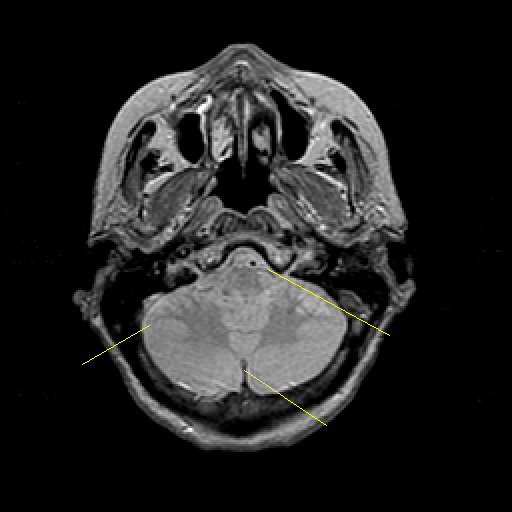

Proton density-weighted structural MR: Slice 10

Slice 10

Pointers